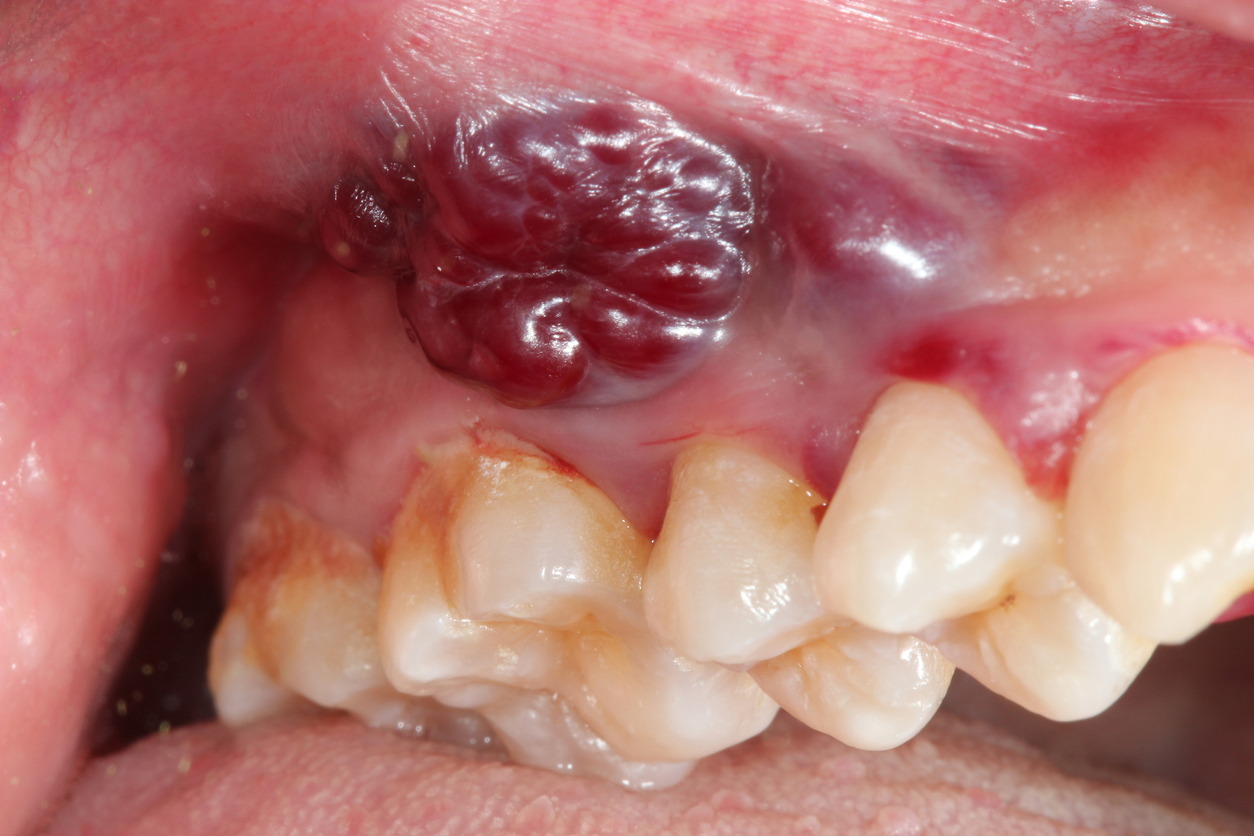

3. 입안 또는 혀에 생긴 덩어리

볼록하거나 딱딱한 혹 같은 덩어리가 만져지고 점점 커진다면, 정밀 검사가 필요합니다.